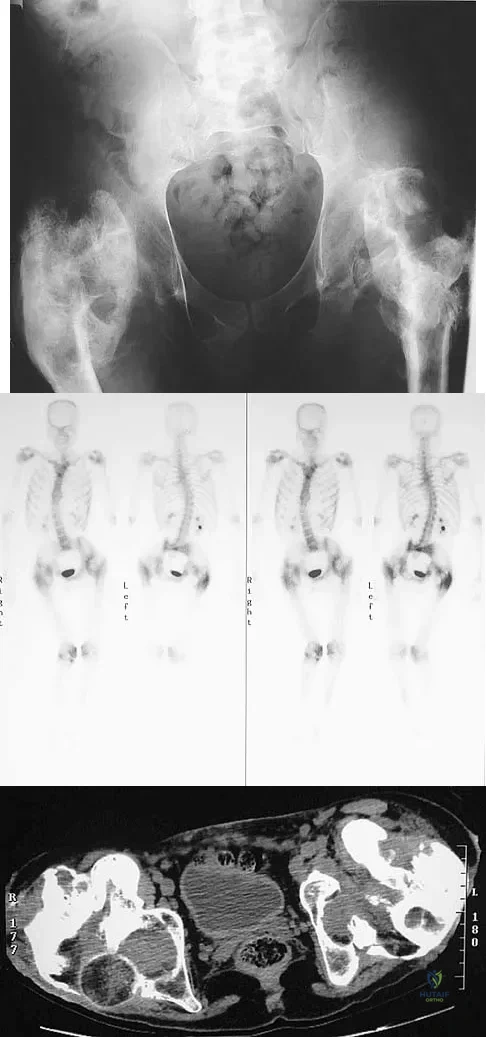

Figure 11a shows the AP pelvis radiograph of a 25-year-old man who sustained a spinal cord injury 10 years ago. A bone scan and a CT scan are shown in Figures 11b and 11c. To prevent recurrence after resection, management should consist of

Explanation